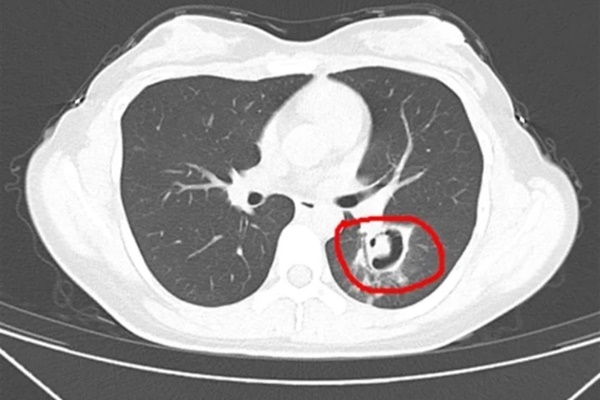

Sau 72 giờ hồi sức tích cực, bệnh nhi đã vượt qua giai đoạn nguy kịch của sốc nhiễm khuẩn, nhưng lại phải đối diện với tình trạng viêm phổi nặng, hoại tử toàn bộ 2 phổi kèm tràn máu, tràn mủ màng phổi gây suy hô hấp nặng.